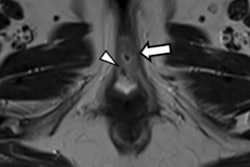

Sagittal images of a normal brain. mTIs nulling white matter (A), mTIi nulling gray matter (B), SIR (mTIs -- mTIi) in (C) and rSIR (mTIi -- mTIs) in (D). There is high gray white matter contrast with gray matter high signal and white matter low signal in (C). In (D) the gray white matter contrast is reversed with white matter white, and gray matter black. Cerebral spinal fluid is of intermediate signal near the noise level in both (C) and (D). SIR, subtracted inversion recovery; TI, inversion time; rSIR, reversed subtraction inversion recovery. Image courtesy of Drs. Ya-Jun Ma, Hongda Shao, Shujuan Fan, Xing Lu, Jiang Du, Ian R. Young, and Graeme M. Bydder and Quantitative Imaging in Medicine and Surgery, October 2020.The tissue properties-filters approach, on the other hand, treats pulse sequences as filters of tissue properties and shows them in graphical form, including the voxel signal S, the contrast, and the sequence weighting (slope of the filter) for each tissue property.